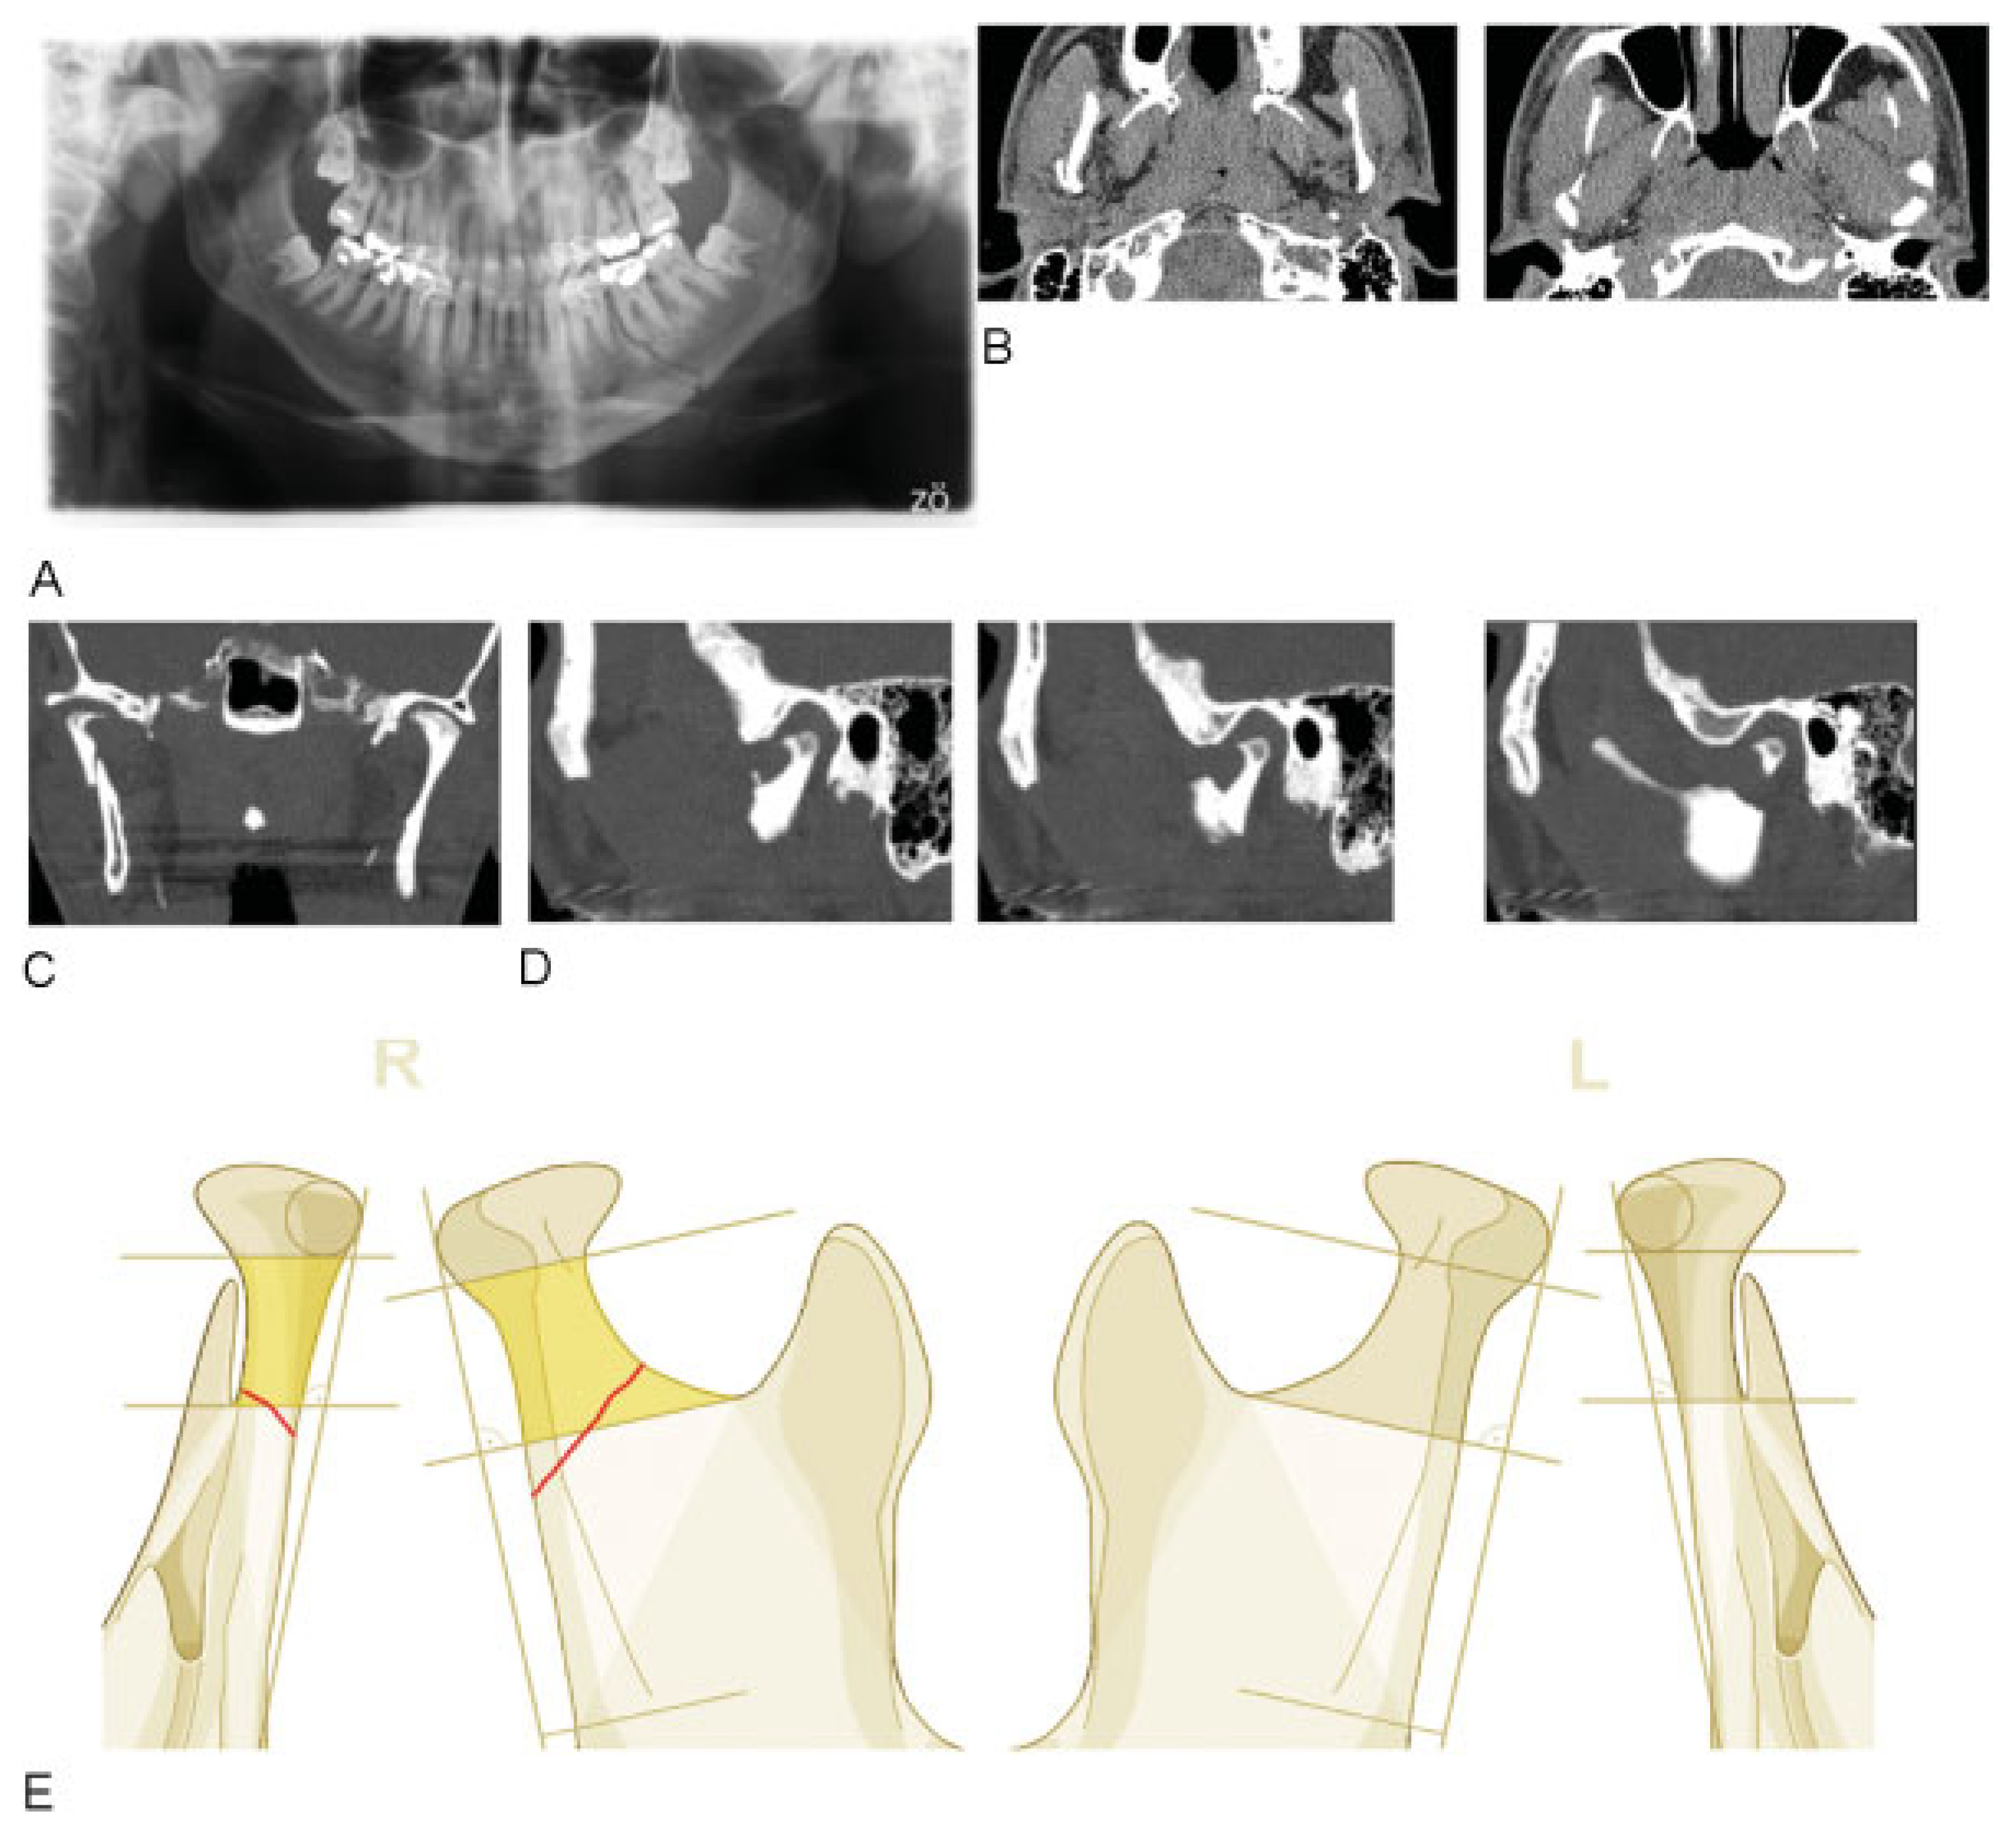

A few case examples are presented to illustrate the classification process. The first case example (Figure 11) shows a typical base fracture (right hand side) with lateral override. The fracture height can easily be identified via OPG (orthopanto-mogram) allowing for the application of the Loukota-line. [4] Alternatively, in case of solely computed tomography (CT)-based diagnostics, the slices with the most caudal position of the small fragment must be assessed preferably in coronal and sagittal views, the latter ones then being mandatory for the definition of the fracture level.

Figure 11. Unilateral condylar base fractures with lateral override. Imaging: X-rays OPG (A), CT axial views (B), CT coronal views (C), CT sagittal views (D). Description: Nonfragmented condylar base fracture right hand side, with complete anterolateral sideward displacement, medial angulation up to 45 degrees, no displacement of the condylar head with regard to the fossa, however dystopic. A loss of ramus height is noted. (E) Level 2 Code: 91 P. Level 3: B0. This case example CMTR-91-101 is made available electronically for viewing using the AOCOIAC software at www. aocmf.org/classification.